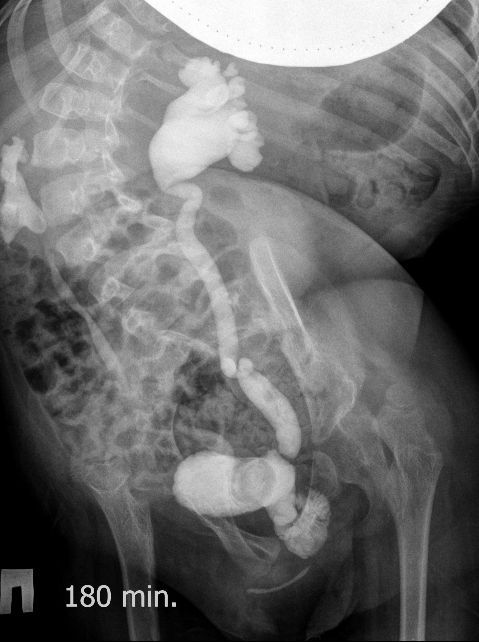

Поскольку откликов нет, добавляю экскреторные урограммы этого же пациента

DX0001.jpg

DX0002.jpg

DX0003.jpg

DX0004.jpg

DX0005.jpg

Нейрогенный мочевой пузырь (?), МКБ, конкремент мочевого пузыря, двухсторонний мегауретер, конкремент правой почки.